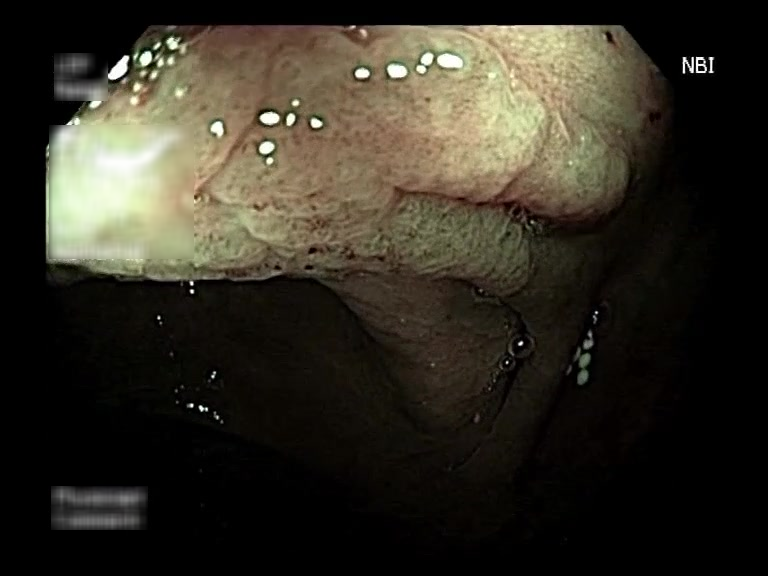

| Lesion | White Light Frame | NBI Frame | White Light Video | NBI Video | Camera Calibration |

| hyperplasic_01 |  |

|

WL.mp4 | NBI.mp4 | cam.xml |